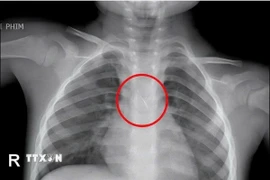

Phim chụp X-Quang dị vật trong cơ thể của bệnh nhân. (Ảnh: PV/Vietnam+)

Sau đó bệnh nhân xuất hiện ho nhẹ kéo dài. Đến ngày 25/11, ho tăng nhiều khiến gia đình đưa đi khám và chụp X-quang, phát hiện dị vật nằm trong phế quản phải nên chuyển gấp đến Bệnh viện Hữu Nghị.